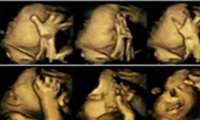

عکسهای تکاندهنده از اثر سیگار بر جنین

این حقیقت که سیگار کشیدن مادر در دوران بارداری یا قبل از آن چه تاثیرات منفی بر جنین میگذارد بر کسی پوشیده نیست اما برخی افراد این موضوع را جدی نمیگیرند ...